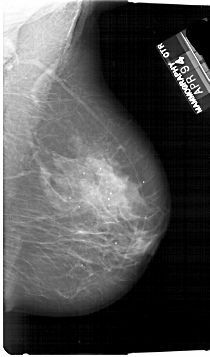

A_1728_1.RIGHT_CC

RIGHT_CC LINES 6856 PIXELS_PER_LINE 3841 BITS_PER_PIXEL 12 RESOLUTION 43.5 NON_OVERLAY